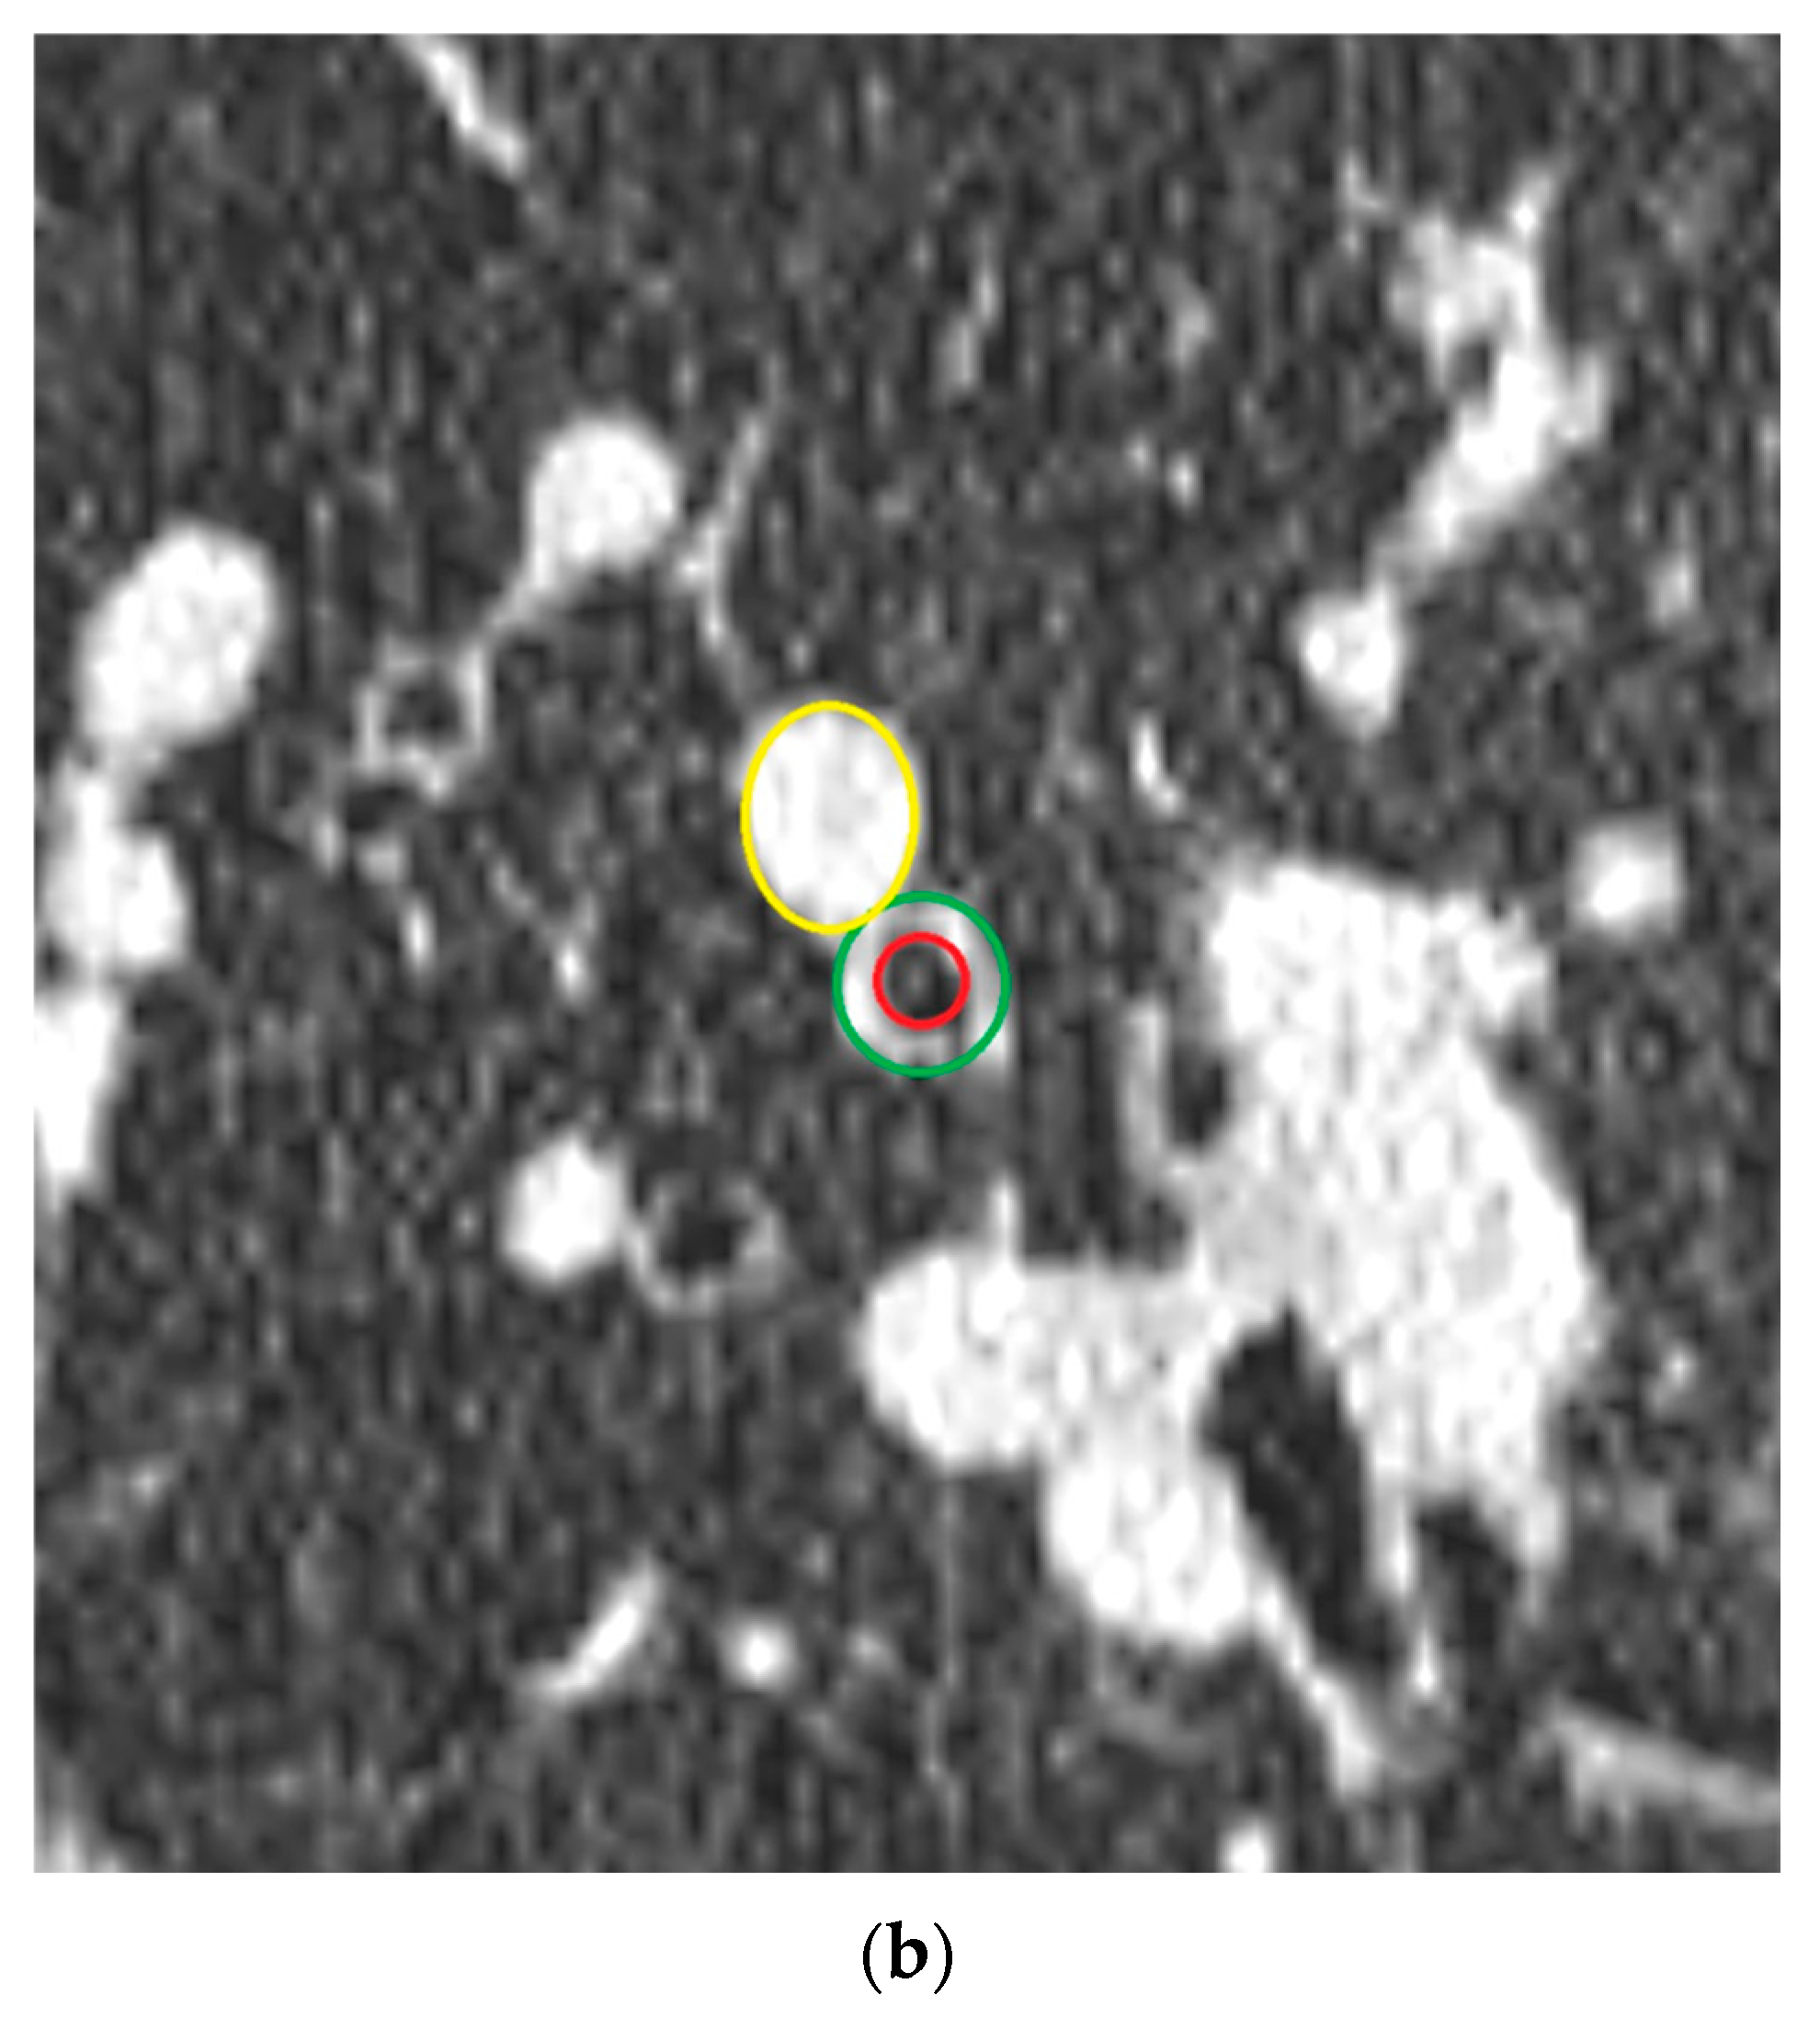

2.3. Quantitative Airway Measurement

2.4. Airway-Artery Pair Analysis